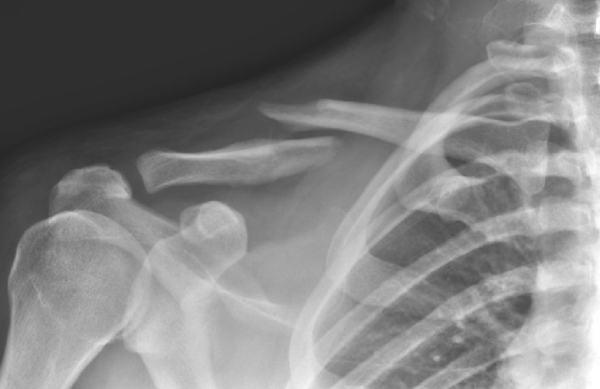

Новообразования ребер и грудной клетки

Классификация опухолей

Опухоли делятся на следующие типы:

- Хондросаркома. Возникает в хрящевых составляющих ребер.

- Ретикулосаркома. Локализуется в сосудистых составляющих.

- Остеосаркома. Находится в костной ткани.

- Фибросакрома. Располагается в сухожильно-связочном аппарате грудины.

Симптоматика

Ранние стадии опухоли зачастую не имеют признаков. В процессе роста новообразования больные ощущают боли под грудью и в области грудной клетки, периодические повышения температуры тела. Иногда при дыхании появляется дискомфорт. Со временем боли становятся сильнее и проявляют себя даже ночью. Если образование разрастается во внешнюю сторону, то при визуальном осмотре около ребра заметно уплотнение.

На последних стадиях ракового заболевания наблюдаются острые боли, которые не помогают унять обезболивающие лекарственные препараты. Новообразование начинает выделять злокачественные клетки, попадающие в кровеносную систему. Метастазы попадают в пищевод, легкие и лимфатические узлы. В это время пациент жалуется на раковую интоксикацию в виде повышенной утомляемости, общего ухудшения состояния здоровья, снижения аппетита и похудения.

Диагностика

Для начала доктор проводит визуальный осмотр, после чего отправляет пациента на следующие обследования:

- рентгенология органов грудины;

- компьютерная томография;

- магнитно-резонансная томография;

- биопсия.